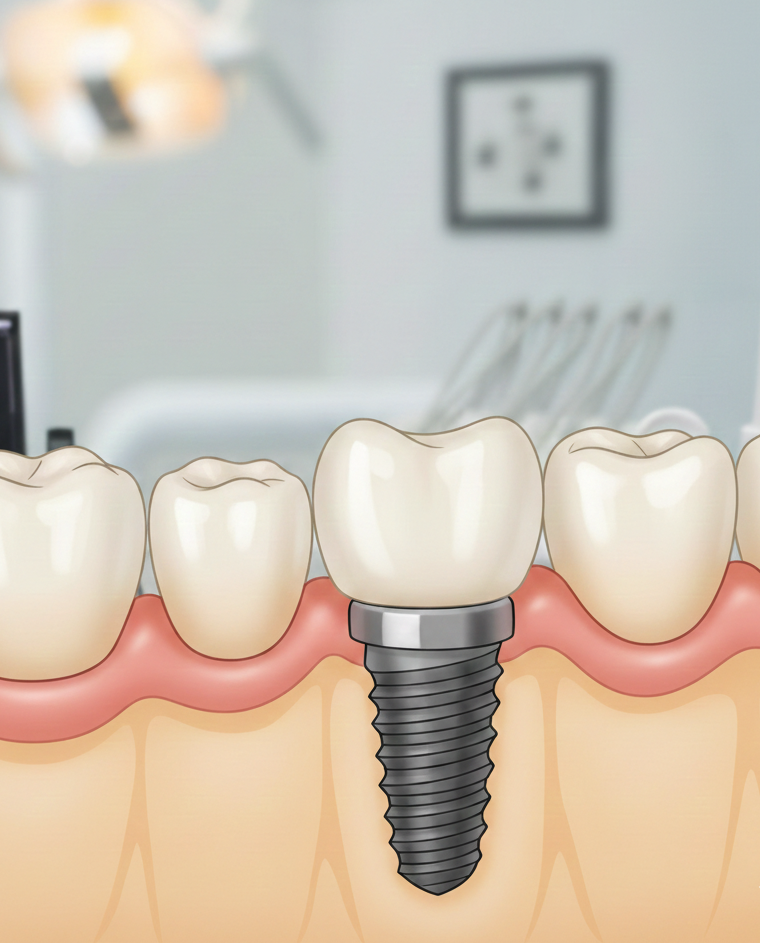

Prótesis sobre Implantes

La prótesis sobre implantes es una de las soluciones más avanzadas y eficaces para devolver la funcionalidad y la estética a la sonrisa. En DigitalLab Churriana, somos especialistas en la fabricación de prótesis sobre implantes en Málaga, combinando precisión técnica, materiales de alta calidad y un enfoque totalmente personalizado.

Nuestro objetivo es ofrecer resultados duraderos,